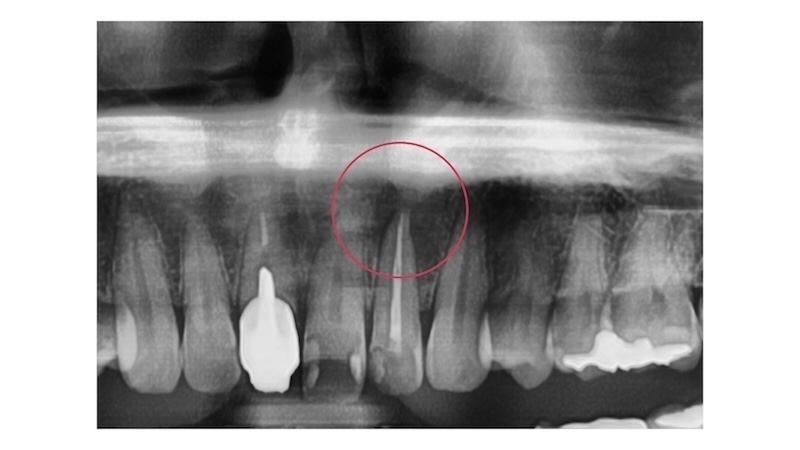

全体の骨や歯の状態を2Dで確認するレントゲン

骨の欠損と感染の広がりを確認